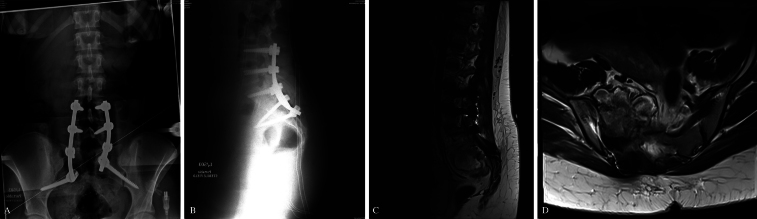

Observations: A 15-year-old girl presented with a 3-month history of right S1-2 radicular pain and right dorsiflexion and plantar flexion weakness. Imaging revealed a right sacral alar aneurysmal bone cyst. The patient underwent right S1-3 hemilaminectomies and partial resection of the S2 and S3 vertebral bodies. Following adequate bony decompression, tumor debulking was performed. Bilateral L4-S1 pedicle screws and left S2AI screws were then placed using neuronavigation guidance. Due to right S1-2 sacral resection, S2AI screw placement was unfeasible. Right-S3 alar-iliac (S3AI) screw placement was performed, and good sacropelvic fixation was demonstrated. Herein, the authors describe the first clinical application of S3AI screw placement in a pediatric patient. After surgery, the patient experienced an improvement in symptoms before later tumor recurrence, which required adjuvant therapy. Long term follow-up revealed solid fusion with stable spinal alignment.

Lessons: In select patients in whom S2AI screw placement is not an option, S3AI screw placement is a feasible, safe, alternative for sacropelvic fixation. https://thejns.org/doi/10.3171/CASE25267.